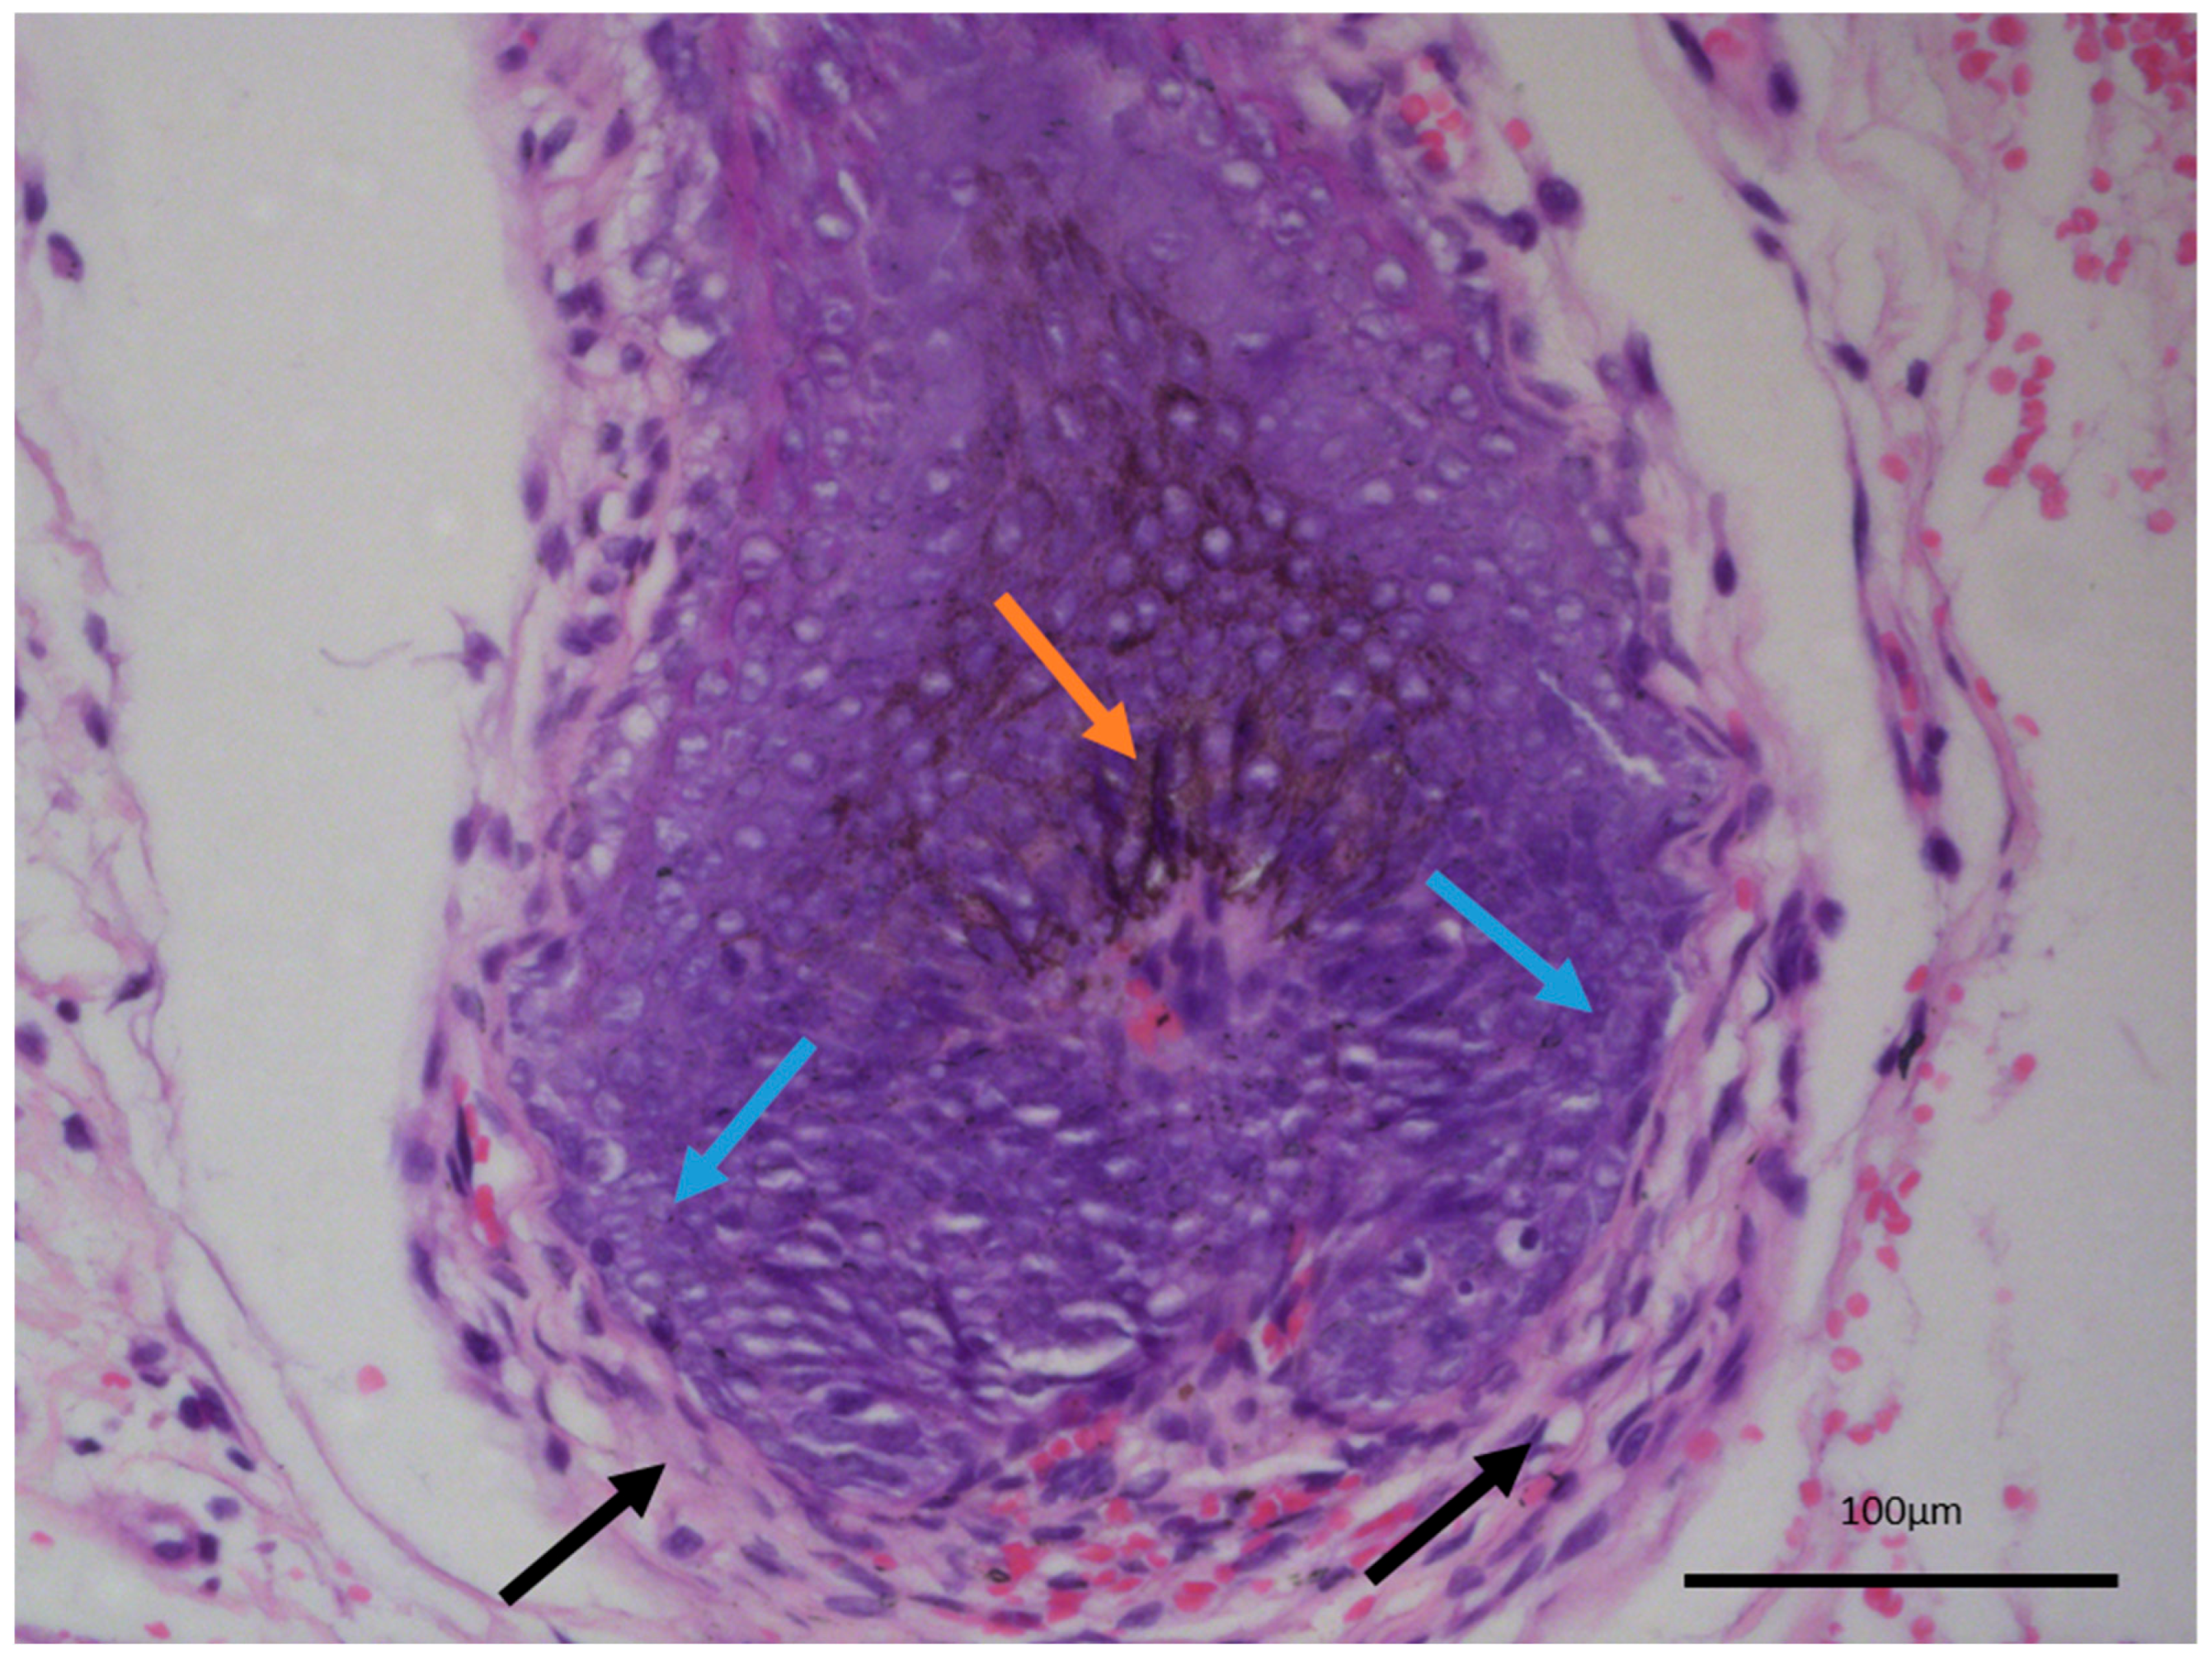

Grossly, the excited specimen was represented by normal cutis and subcutis and fleshy brown tissue with a nodular appearance. Histopathology showed intact epidermis and dermis with a deeply located, basaloid nested tumor within the reticular dermis, with extensive brown pigment deposition (Figure 1). The tumor itself was located deep in the dermis with subcutaneous extension and was sharply demarcated from the surrounding tissues, with a focal appearance of an intracystic tumor due to significant detachments from them. Growth pattern was represented by nests of various calibers and reticular-papillary structures, with some of the nests exhibiting a basaloid appearance and focal peripheral palisading with a complete absence of epidermal and cutaneous–adnexal connection. Some of the nests formed primitive hair follicular rudiments with mesenchymal papillary bodies and pronounced basaloid type morphology. Larger tumor cell nests had foci of interstitial edema with the formation of cystic spaces of various calibers, focally filled with eosinophilic matter, including areas similar to primitive hair structures. In these nests, the cells were large with central bright nuclei and marginated chromatin, without clearly visible boundaries between the cells. Focally degenerative type atypia was noted along with sparse mitoses in the entire tumor population. Some areas showed an onion-skin-like cellular arrangement of paler cells. The tumor itself was extensively colonized by melanocytes with pronounced melanin production and incontinence with accumulation of pigment in a small part of the peripheral tumor cells, pigmented macrophages, and freely in the intercellular space.

Figure 1.

Histopathology of the tumor: (A) Large nodular growth pattern (blue arrow) and foci of extensive pigment deposition (orange arrows), H&E stain, original magnification 50×. (B) Reticular growth pattern (blue arrow) with foci of pigment deposition (orange arrow), H&E stain, original magnification 100×. (C) Wrapping hypercellular stroma with focal papillary mesenchymal bodies-like structures (black arrows) and intertumor pigment deposition (orange arrow), H&E stain, original magnification 200×. (D) Peripheral tumor cell palisading without clefting (blue arrows) towards the wrapping and intersecting hypercellular stroma (black arrows), H&E stain, original magnification 400×.

The last differential diagnosis of melanotrichoblastoma, due to its prominent pigment cell component, is that of melanoma [14,15]. While there is a melanocytic component within the tumor, both based on morphology and their immunophenotype characteristic, these are completely benign cells within the tumor, recapitulating the naturally occurring dendritic melanocytes of the hair follicles, which give out their melanin pigment to the hair shaft and color the hair. As such, melanotrichoblastomas not only represent a benign tumor, but can be viewed as the best differentiated variety of trichoblastoma as they completely reenact the structure of the hair follicle—epithelial, mesenchymal, and melanocytic components—with only the growth pattern differing from a normal hair follicle (Figure 4).

Normal hair follicle histology, internal control from adjacent non-involved tissues from the same patient. Dendritic melanocytes (orange arrow), palisading epithelial cells (blue arrows), and hypercellular wrapping stroma (black arrows), original magnification 200×.